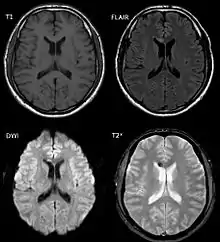

![]() صورتين بالرنين المغناطيسي لمريض لديه إصابة محورية منتشرة. صورتين بالرنين المغناطيسي لمريض لديه إصابة محورية منتشرة. | |

تُسبب الإصابة المحورية المنتشرة آفات صغيرة تظهر تحت المجهر بوضوح، لكن يصعب اكتشافها في التصوير المقطعي أو في تقنيات التصوير العياني الأخرى اعتمادا على بعض خصائصها، ولكن يمكن استنتاج وجود إصابة محورية منتشرة عندما وجود نزيف صغير مرئي في الجسم الثفني أو القشرة الدماغية،[29] ويُعد التصوير بالرنين المغناطيسي أكثر فائدة عند البحث عن خصائص الإصابة المحورية المنتشرة، فالدراسات الحديثة متل صورة الانتشار في الرنين المغناطيسي القدرة على إثبات درجة إصابة المادة البيضاء حتى عند عدم ظهور ذلك في التصوير بالرنين المغناطيسي المعتاد. ونظرًا لأن التلف المحوري في الإصابة المحورية المنتشرة ينتج بسبب التسلسل الكيميائي الحيوي الثانوي، ومن ثَم فقد يتدهور الشخص المصاب رغم أنه كان طبيعيا في البداية، وعليه فإن الإصابة في كثير من الأحيان تكون أكثر شدة مما هو متوقع، ويجب أن يشتبه الأطباء في الإصابة المحورية المنتشرة في المرضى الذين تبدو فحوصاتهم المقطعية المحوسبة طبيعية ولكن لديهم أعراض مثل فقدان الوعي.